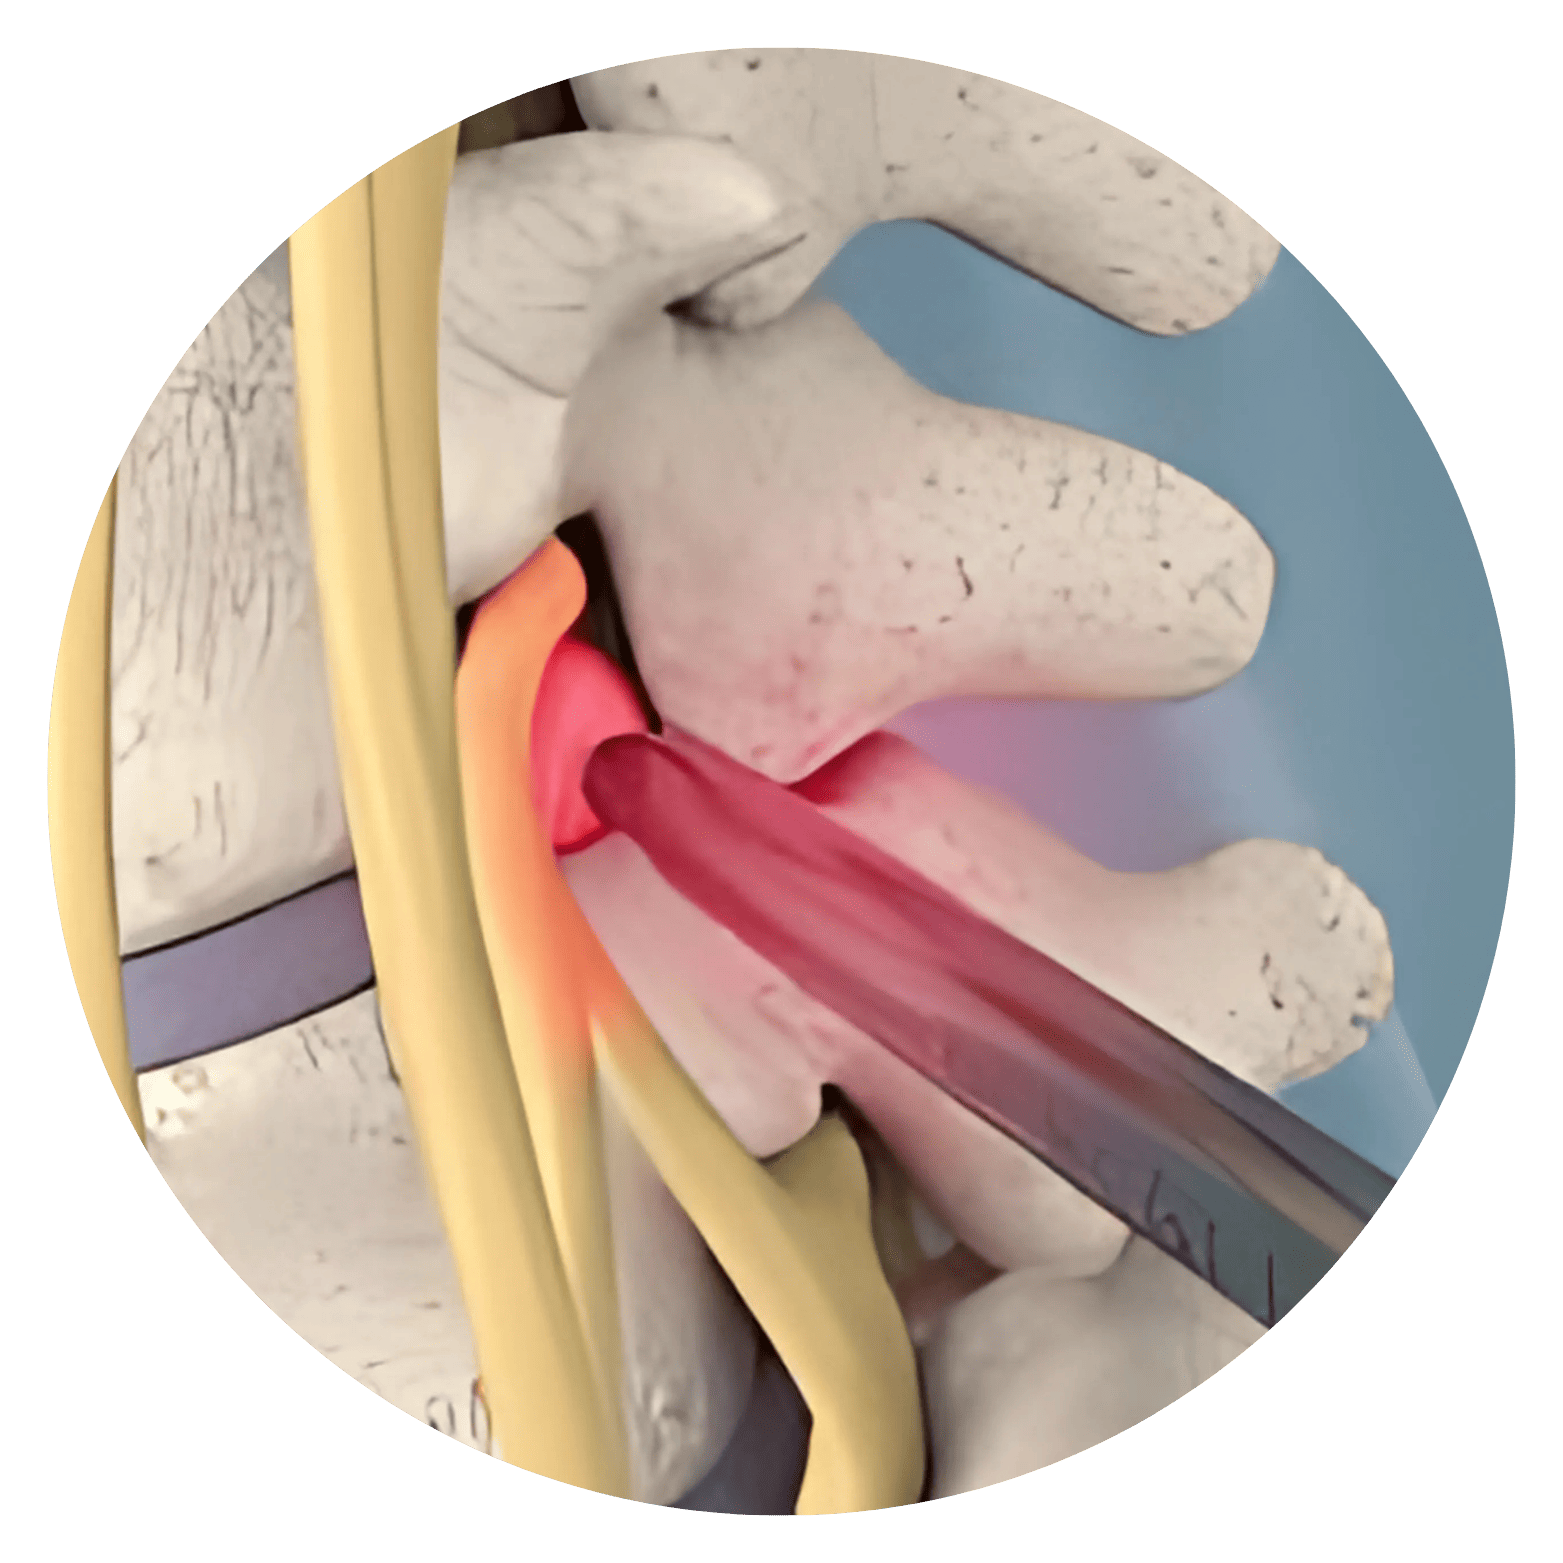

Hérnia de Disco Lombar Aquela dor insuportável na região lombar que impede o simples ato de amarrar os sapatos, ou uma pontada aguda que desce